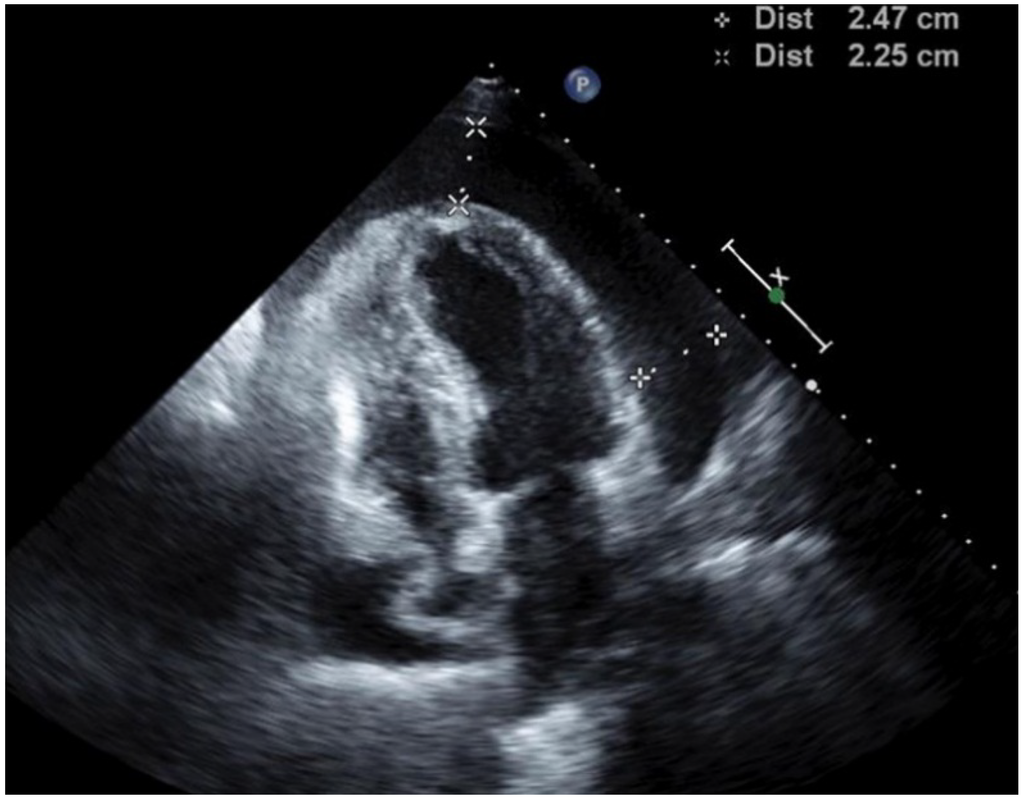

3. Case 2